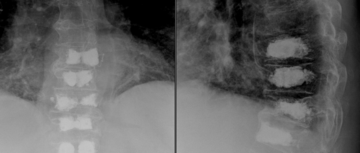

Die Kyphoplastie ist ein minimalinvasives Verfahren zur Behandlung von osteoporotischen Wirbelkörperbrüchen. Hierbei werden zwei Hohlnadeln in den betroffenen Wirbelkörper eingebracht. Durch diese Nadeln wird ein kleiner, flüssigkeitsgefüllter Ballon eingeführt, der den gebrochenen Wirbelkörper aufrichtet. Der dadurch entstehende Hohlraum wird anschließend mit speziellem Zement gefüllt, um den Wirbel zu stabilisieren.

Da osteoporotische Wirbelkörperbrüche in der Regel stabile Brüche sind, ist es in den meisten Fällen nicht notwendig, den betroffenen Wirbelsäulenabschnitt zusätzlich durch ein Schrauben-Stab-System zu stabilisieren.

Kyphoplastie mehrerer Brustwirbelkörper bei Brüchen der Brustwirbelsäule (Multiples Myelom).